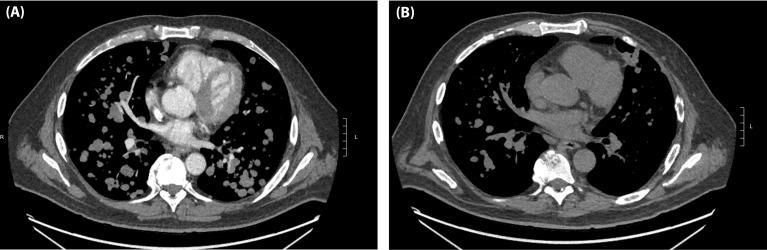

晚期黑色素瘤患者接受伊匹单抗/纳武单抗联合治疗的早期反应评估。

Early Response Assessment in Advanced Stage Melanoma Treated with Combination Ipilimumab/Nivolumab.

Standard combination ipilimumab/nivolumab (I/N) is given as 4 induction doses for advanced stage melanoma followed by nivolumab single-agent maintenance therapy. While many patients receive less than 4 doses due to immune-related toxicities, it is unclear if fewer doses of I/N may still provide long term clinical benefit. Our aim is to determine if response assessment after 1 or 2 doses of I/N can predict long-term survival and assess if fewer doses of I/N can lead to similar survival outcomes.

We performed a retrospective analysis on a cohort of patients with advanced melanoma who w0ere treated with standard I/N. Cox regression of progression-free survival (PFS) and overall survival (OS) models were performed to assess the relationship between response after 1 or 2 doses of I/N and risk of progression and/or death. Clinical benefit response (CBR) was assessed, defined as SD (stable disease) + PR (partial response) + CR (complete response) by imaging. Among patients who achieved a CBR after 1 or 2 doses of I/N, a multivariable Cox regression of survival was used to compare 1 or 2 vs 3 or 4 doses of I/N adjusted by known prognostic variables in advanced melanoma.

RESULTS

199 patients were evaluated. Patients with CBR after 1 dose of I/N had improved PFS (HR: 0.16, 95% CI 0.08-0.33; p<0.001) and OS (HR: 0.12, 0.05-0.32; p<0.001) compared to progressive disease (PD). Patients with CBR (vs PD) after 2 doses of I/N also had improved PFS (HR: 0.09, 0.05-0.16; p<0.001) and OS (HR: 0.07, 0.03-0.14; p<0.001). There was no survival risk difference comparing 1 or 2 vs 3 or 4 doses of I/N for PFS (HR: 0.95, 0.37-2.48; p=0.921) and OS (HR: 1.04, 0.22-4.78; p=0.965).

CONCLUSIONS

Early interval imaging with response during induction with I/N may be predictive of long-term survival in advanced stage melanoma. CBR after 1 or 2 doses of I/N is associated with favorable survival outcomes, even in the setting of fewer I/N doses received. Further studies are warranted to evaluate if electively administering fewer combination I/N doses despite tolerance in select patients may balance the benefits of therapy while decreasing toxicities.